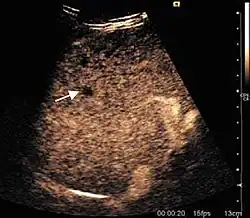

HCC appearance on 2D ultrasound is that of a solid tumor, with imprecise delineation, with heterogeneous structure, uni- or multilocular (encephaloid form). An "infiltrative" type is also described which is difficult to discriminate from liver nodular reconstruction in cirrhosis. Typically HCC invades liver vessels, primarily the portal veins but also the hepatic veins . Doppler examination detects a high speed arterial flow and low impedance index (correlated with described changes in tumor angiogenesis). The spatial distribution of the vessels is irregular, disordered. CEUS examination shows hyperenhancement of the lesion during the arterial phase. During the portal venous phase there is a specific "wash out" of ultrasound contrast agent (UCA) and the tumor appears hypoechoic during the late phase. Poorly differentiated tumors may have a stronger wash out leading to an isoechoic appearance to the liver parenchyma during portal venous phase. This appearance was found in approx. 30% of cases. The described changes have diagnostic value in liver nodules larger than 2 cm.